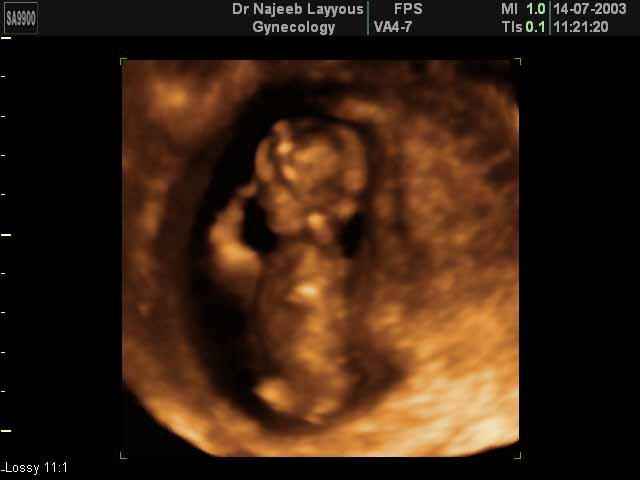

- 3D Photos Ecographie du Premier Trimestre

3D Photos Ecographie du Premier Trimestre (Photos d’échographie de tôt grossesse)| Dr N Layyous